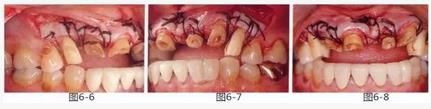

圖6-6~8

左上3到右上3的牙齒,通過包含牙槽骨外科處理在內(nèi)的APF進(jìn)行治療,確保了獲得biologic width所必需的、3mm以上的健全牙體組織。為獲得附著齦,使用FGG對左上4和右上4的牙齒進(jìn)行了治療。

圖6-9 牙周外科治療5個月后,最終取模前的狀態(tài)?;乐車@得了充足的附著齦。

圖6-10 佩戴最終修復(fù)體時的X光照片。